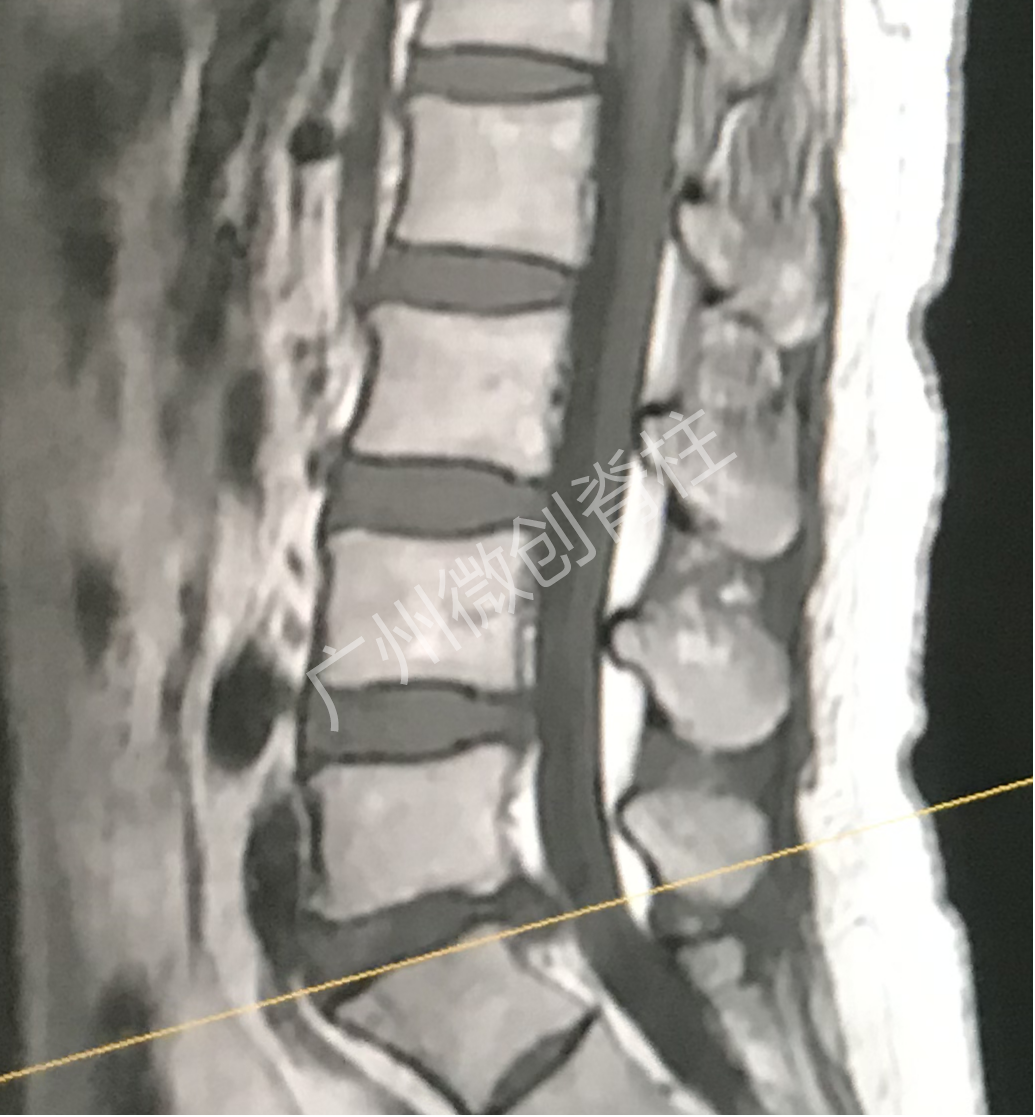

50多岁的女性患者,腰痛伴左下肢麻痛3年多,久坐或长时间行走后加重,在外院多次予按摩、针灸、贴药膏等治疗,症状未见明显好转,严重困扰日常生活及工作,为进一步诊治,遂来广州医科大学附属第一医院脊柱外科找到何二兴主任就诊,何二兴主任了解了患者病史及体征,结合x光、CT及MR检查结果,诊断为腰椎间盘突出症,患者腰5骶1节段有大块椎间盘突出,压迫神经,引起神经性疼痛。

何二兴主任治疗团队对患者的病情进行了详细的研究,决定利用微创手段,使用内窥镜辅助方法,顺利帮助患者解决了困扰3年多的痛苦。患者恢复很快,术后第一天就可以佩戴腰围下地行走。手术伤口如硬币大小,伤口愈合后疤痕挛缩伤口更小。